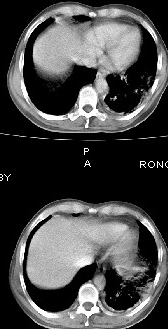

男68岁,反复发热、咳嗽,咯痰1月,曾有咯血史,双肺闻及呼吸音增粗。

左肺上叶尖后段及下叶多发实变阴影,内见支气管充气征,段以上支气管尚通畅,肺门区未见软组织肿块影,结合病人有反复发热病史,首先考虑感染性病变(干酪性肺炎不能排除),建议抗炎治疗后复查或结合纤支镜检查。

左肺上叶尖段及下叶干酪性肺炎可能性大,建议结合临床相关检查.右肺中叶炎症.建议治疗后复查.

该患者在25天前外圆平片见右肺中上肺野大片状影,(治疗不祥,在反复问病史后患者告诉;近一月住在新房内,搞装修),我认为首先考虑是感染,而且过敏性肺炎可能性大。

右肺中叶左肺下叶感染。